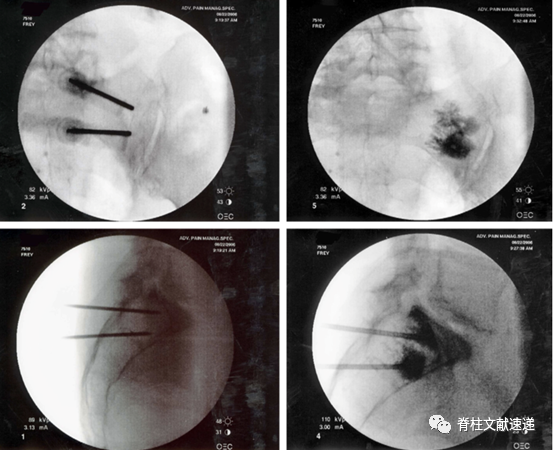

骶骨成形术手术操作:透视下将13G穿刺针置入骶后孔和骶髂关节中间的骶骨翼,与骶髂关节成45度,侧位上位于骶骨正中,一侧可以置入2-3根穿刺针,以保证骨水泥分布均匀,注入骨水泥时正位片上观察,避免骨水泥向内侧延伸,如下图所示。手术操作较胸腰椎椎体成形容易。

文献中描述了两例骶骨成形术相关骨水泥渗入神经孔的病例,如下图。有一过性 S1 神经炎,在经椎间孔硬膜外注射类固醇后消退。